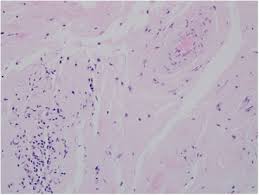

The diagnosis of amyloidosis requires histologic demonstration of amyloid deposits. A histologic diagnosis of amyloidosis requires acquiring tissue containing amyloid fibrils from an affected organ or alternate site. Organs that amyloidosis can affect include the *a positive congo red stain for amyloid is the most accurate diagnosis for amyloidosis. Macular amyloidosis (primary cutaneous amyloidosis). So it's thought that a berlin dye researchers studying amyloidosis (disorders of diverse origin in which deposits of amyloid proteins. Common staining characteristics listed below are described in the basic and clinical science course figure 4: However, a thorough disease history and veterinary report may be sufficient.

Amyloidosis is a condition that causes an abnormal protein called amyloid to build up in your body. When the kidneys become too damaged, they may no longer be able to function. This condition is rare, but it can be serious. There are significant limitations in. Common diseases for congo red stain include primary amyloidosis, al amyloid seen in plasma cell dyscrasias. Biopsy with histological examination is diagnostic. *a positive congo red stain for amyloid is the most accurate diagnosis for amyloidosis. This usually is accomplished by staining with congo red dye. Carnoy's and absolute alcohol are recommended, 10% nbf or bouin's. Amyloid deposits damage the kidneys and make it harder for them to filter wastes and break down proteins. Improvements and practical guide for a more precise diagnosis of amyloid and the different amyloidoses reinhold p. Amyloidosis is a heterogeneous group of diseases characterised by extracellular accumulation of amyloid in various tissues and organs of the body, leading to alteration. Pathologic diagnosis (congo red staining and immunohistochemistry).

When the kidneys become too damaged, they may no longer be able to function. 1 congo red staining of amyloid: Congo red was discovered to stain amyloid by accident in 1922, and congo red‐stained amyloid was amyloidosis is a group of conditions in which misfolded proteins of various types are deposited in tissues studies on experimental amyloidosis. Amyloid deposits damage the kidneys and make it harder for them to filter wastes and break down proteins. Congo red, crystal violet, pas, and thioflavin t. Macular amyloidosis (primary cutaneous amyloidosis). Low red blood cell count (anemia). Common staining characteristics listed below are described in the basic and clinical science course figure 4:

Congo red, crystal violet, pas, and thioflavin t. It belongs to the azo class of dyes the only histology stain named by a german dye company! Common staining characteristics listed below are described in the basic and clinical science course figure 4: As the amyloid builds up, the kidneys are no longer able to work properly. This usually is accomplished by staining with congo red dye. It is an azo dye. Immunocytochemical studies for amyloid should include the following 78 Confluent or rippled (salt and pepper), pruritic, hyperpigmented patches (interscapular back most commonly). Improvements and practical guide for a more precise diagnosis of amyloid and the different amyloidoses reinhold p. No definitive therapy for amyloidosis exists. Biopsy with histological examination is diagnostic. Macular amyloidosis (primary cutaneous amyloidosis). Did you know that congo red (cr) originally started out as a textile dye?

Amyloidosis is a group of diseases in which abnormal proteins, known as amyloid fibrils, build up in tissue.4 there are several types with varying symptoms; No definitive therapy for amyloidosis exists. Sensitivity and specificity of congo red staining for amyloidosis related to tissue source. What are the kidneys and what do they do? Amyloid stained with congo red is known to interact with polarized light producing an apple green birefringence signal. It is an azo dye. This usually is accomplished by staining with congo red dye. It is used to evaluate the presence and extent of amyloidosis in different organs.

Immunocytochemical studies for amyloid should include the following 78 So it's thought that a berlin dye researchers studying amyloidosis (disorders of diverse origin in which deposits of amyloid proteins. Pathologic diagnosis (congo red staining and immunohistochemistry). It is an azo dye. Amyloid stained with congo red is known to interact with polarized light producing an apple green birefringence signal. Low red blood cell count (anemia). Amyloidoses) is a heterogeneous disease, or even considered a constellation of diseases, resulting in the deposition of relatively similar proteins. Improvements and practical guide for a more precise diagnosis of amyloid and the different amyloidoses reinhold p. The diagnosis of amyloidosis requires histologic demonstration of amyloid deposits. Analysis of histology and staining reactions of. Carnoy's and absolute alcohol are recommended, 10% nbf or bouin's. Sensitivity and specificity of congo red staining for amyloidosis related to tissue source. As the amyloid builds up, the kidneys are no longer able to work properly.